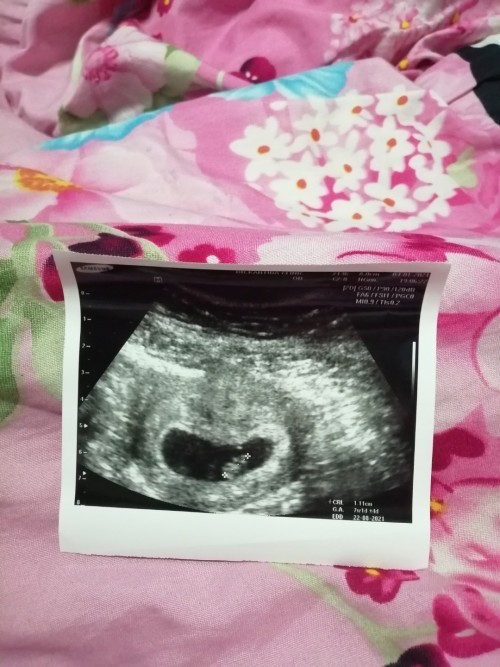

แม่! 🤰💖อวดรูปอัลตร้าซาวด์กัน

โชว์รูปแรกของเบบี้กันหน่อยน้า เพศหญิง👧หรือชาย🧑เอ่ยยย 😍🥰💜 17/09/2563

รอลุ้นอยู่ค่ะ..น้อง 9 สัปดาห์